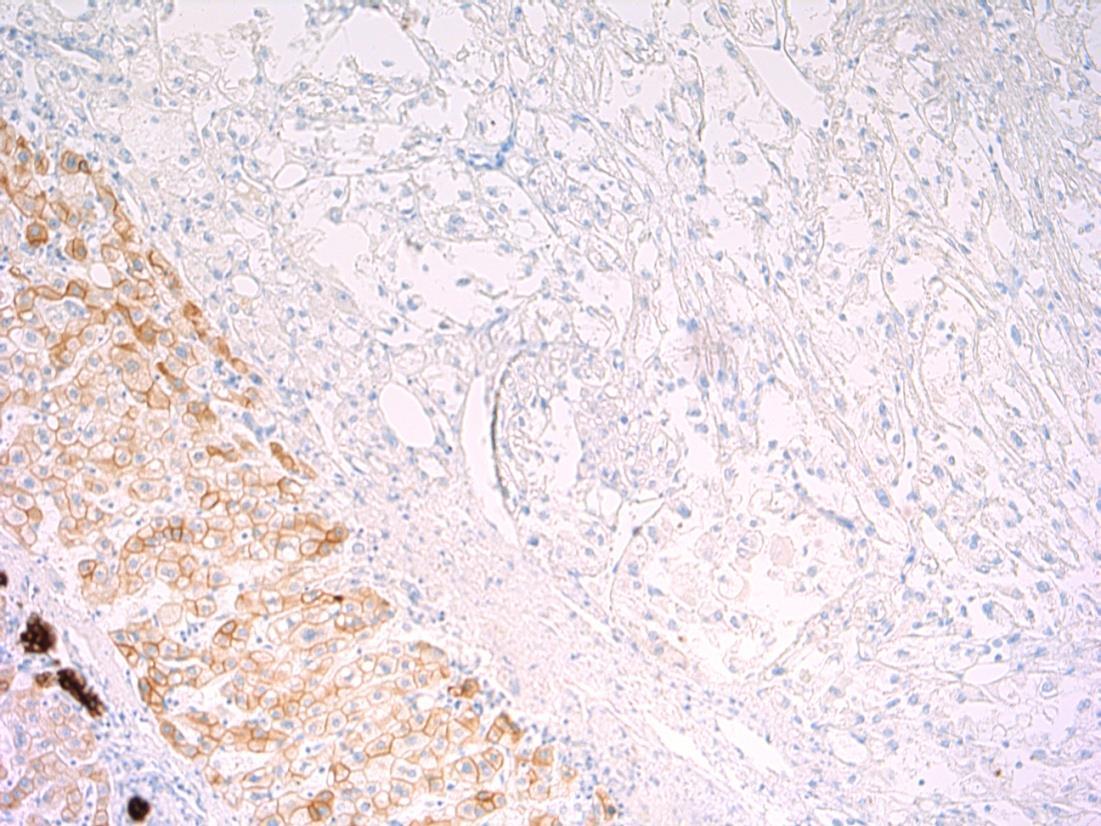

• 80F, with haematuria. Cystoscopy shows a large tumour on the posterior wall. TURBT performed.

Case 5

TURBT - G3 (high-grade) TCC with small cell carcinoma component

Case

5

AE1/3 - TCC AE1/3 – small cell CD56 - TCC CD56 – small cell

cell

- TCC

P63 - TCC

Synapto

small

P63

small cell

G3 (high-grade) TCC with small cell carcinoma component

Description: Biphasic malignant tumour. High grade large epithelial cell component and high grade small round blue cell tumour component. CIS also seen.

Favoured Diagnosis: G3 (high-grade) TCC with small cell carcinoma component. Plan: Correlate with urine cytology/ previous biopsies. IHC: TCC= AE1/3+, p63+, small cell ca = AE1/3 dot +, CD56+, synapto +. Look for invasion into lamina propria and muscle (staging).

Comments: • Small cell carcinoma is frequently admixed with TCC, SCC or adenocarcinoma of bladder • >90% muscle invasive and metastases common, poor prognosis. • Responds to chemotherapy (cisplatin based) • Differential Diagnosis of pure small cell carcinoma: – Poorly-differentiated urothelial carcinoma – Metastatic small cell carcinoma from other site eg lung – Lymphoma – Alveolar rhabdomyosarcoma – Inflammation (in a crushed, cauterised, superficial or scant specimen)

3.5 Associations, prognosis, treatment etc 3.0 Use of IHC for confirmation 2.5 Description with diagnosis, mentions both components 2.0 Only one component mentioned 1.5 Other malignant diagnosis 1.0 Benign diagnosis Case 5